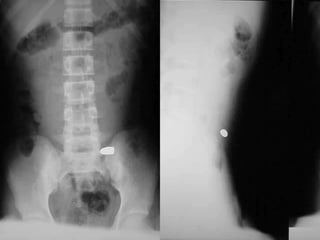

Rx AP y Lateral abdomen en herida por

proyectil arma de fuego.

Urografía, hematuria macro, heridas lumbares.

Cisto uretrografía sospecha lesión uretra o

vejiga